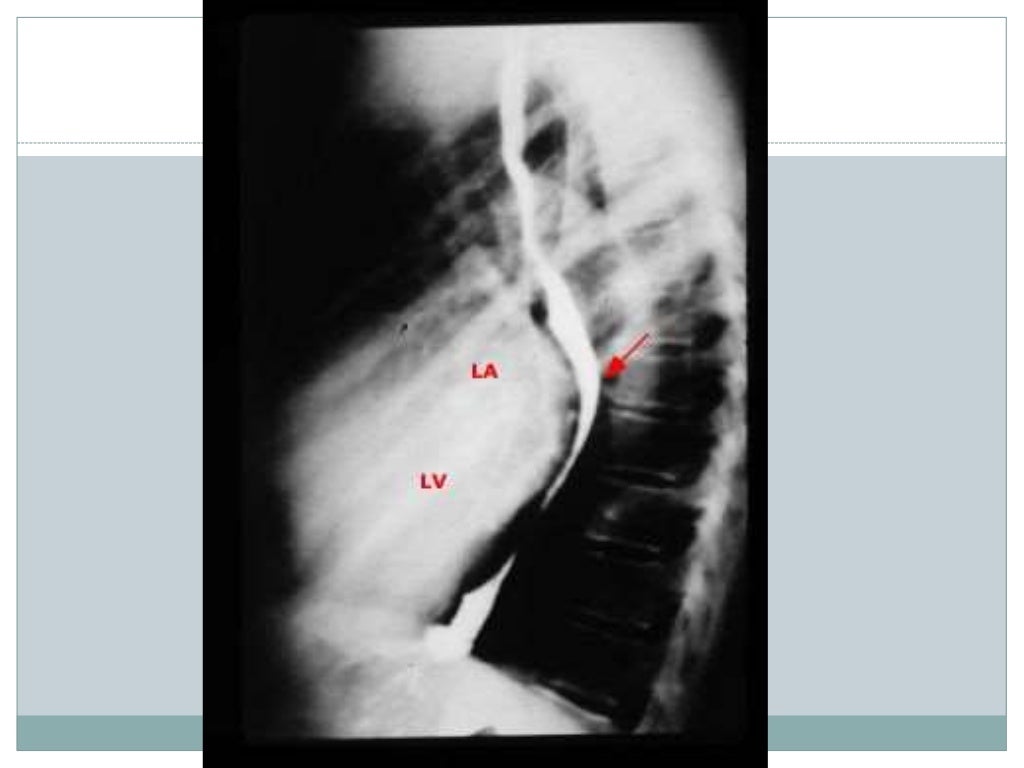

Stenosis mitral radiology imaging larger